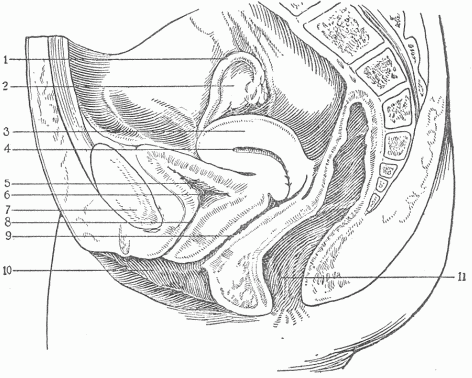

The genito-urinary surface is the smallest of the surfaces. In the male (Fig. 8,—27, 28, 30) this communicates with the general external surface by the small opening at the extremity of the penis, and in the female by the opening into the vagina. In its entirety it consists in a surface of wide extent, comprising in the male the urethra, a long canal which opens into the bladder, and is continuous with ducts that lead into the genital glands or testicles. The internal surface of the bladder is extended by means of two long tubes, the ureters, into the kidneys, and receives the fluid formed in these organs. In the female (Fig 9) there is a shallow external orifice which is continued into the bladder by a short canal, the urethra, the remaining urinary surface being the same as in the male; the external opening also is extended into the short, wide tube of the vagina, which is continuous with the canal of the uterus. This canal is continued on both sides into the Fallopian tubes or oviducts. There is thus in the female a more complete separation of the urinary and the genital surfaces than in the male. Practically all of the waste material of the body which results from cell activity and is passed from the cells into the fluid about them is brought by the blood to the kidneys, and removed by these from the blood, leaving the body as urine.

Fig. 9.—A Longitudinal Section Through The Female Pelvis.

1. The Fallopian tube which forms the connection between

the ovary and the uterus.

2. The ovary.

3. The body of the uterus.

4. The uterine canal.

5. The urinary bladder represented as empty.

6. The entrance of the ureter.

7. The pubic bone.

8. The urethra.

9. The vagina.

10. The common external opening or vulva.

11. The rectum and anus.